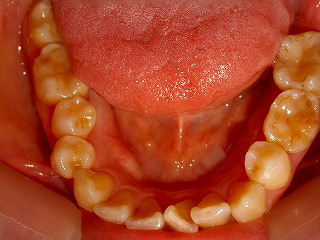

治療後の上顎                        治療後の下顎